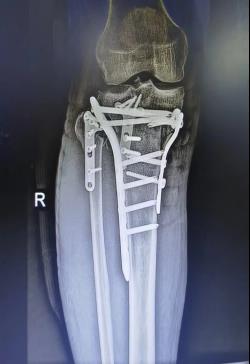

(五)胫骨平台骨折内固定术